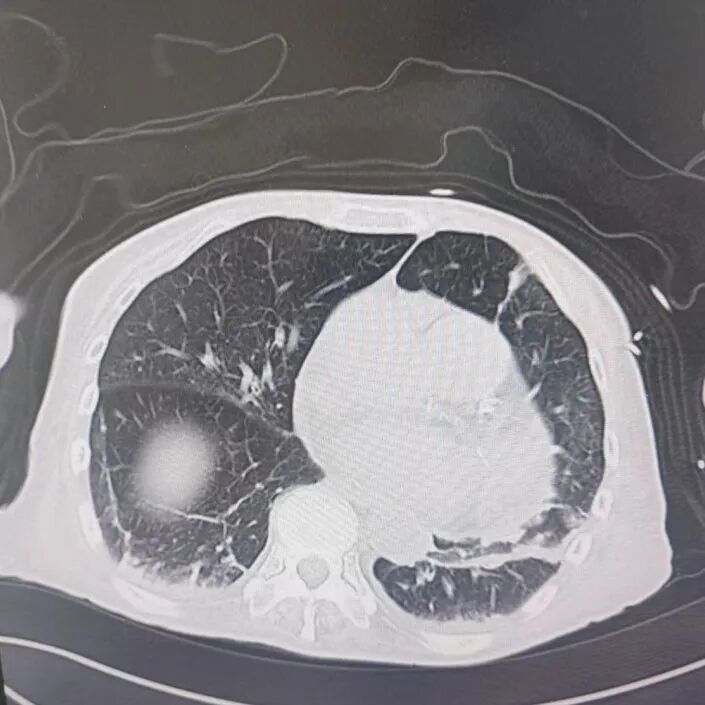

引言 / / Introduction 年近8旬的陈阿姨(化名)因脑梗长期瘫痪在床,康复期间突然高烧不退,体温升至39℃,在抗感染过程中,她并发高渗性脱水,病情急剧恶化,被紧急送入ICU。此时,她已气管切开,依靠呼吸机维持呼吸,并伴有低蛋白血症、低钾高钠血症及房颤等多种危重情况,命悬一线! PART. 01 多重泛耐药菌叠加大量基础病 治疗陷入“死胡同” 呼吸与危重症医学科及ICU通力协作,稳住患者生命体征。治疗过程中,进一步的病原学检查结果令人心惊:陈阿姨的肺部遭遇多种“超级细菌”混合侵袭,包括铜绿假单胞菌、鲍曼不动杆菌、嗜麦芽窄食单胞菌、金黄色葡萄球菌、木糖氧化无色杆菌、粘质沙雷菌等高度耐药菌,堪称耐药菌“大本营”。这些细菌对常用抗生素几乎全部耐药,治疗难度高,死亡率高。 治疗前患者肺部影像 PART. 02 多学科强强联手 量身定制攻坚方案 面对无药可用的困境,呼吸科没有放弃!宋刚主任带领团队联合药学部、检验科、重症医学科成立多学科治疗组,根据患者身体情况实时调整用药,逐一攻破耐药菌。这场与“超级细菌”的拉锯战持续了30多个日夜。 在医护日夜坚守和家属全力配合下,陈阿姨的感染终于被遏制:高烧退了,肺部阴影消散了!就在即将宣告胜利时,又发现她存在泌尿感染问题,随即转入泌尿外科协同治疗。当宋主任回访时,看到陈阿姨精神焕发、体温平稳,所有参与救治的人都感慨万分!这场救治,正是呼吸与危重症医学科攻坚耐药菌硬实力的生动体现! 治疗后患者肺部影像 从“无药可用”到“绝处逢生”,此次成功救治,集中体现了呼吸与危重症医学科以耐药菌精准诊治为核心的学科特色与技术优势。面对一次次的严峻挑战,科室始终秉持“生命至上、知难而进”的信念,以多学科协作为平台,凭借个体化精准用药策略,为患者寻找生机,为更多陷入困境的患者和家庭带去了实实在在的希望。 PART. 03 人民医院 人民名医 宋刚 主任医师 ·葫芦岛市第二人民医院呼吸与危重症医学科主任 ·辽宁省生命科学学会东北呼吸与危重症医学(PCCM)分会辽宁省基层委员会副主任委员 ·辽宁省细胞生物学学会放射粒子治疗专业委员会理事 ·辽宁省抗击新冠肺炎疫情先进个人 ·葫芦岛市劳动鉴定委员会专家库成员 ·葫芦岛市医学会呼吸内科学分会第三届委员会副主任委员 专业特色:擅长呼吸系统疑难及急危重患者的救治,如急慢性支气管炎、支气管哮喘、慢性阻塞性肺疾病、肺炎、肺栓塞、肺癌、间质性肺疾病、睡眠呼吸暂停综合征等,尤其擅长有创无创机械通气、支气管镜下相关检查及治疗(TBNA、气道支架置入术、球囊扩张等)、全肺灌洗术等领先技术,发表国家级期刊多篇。